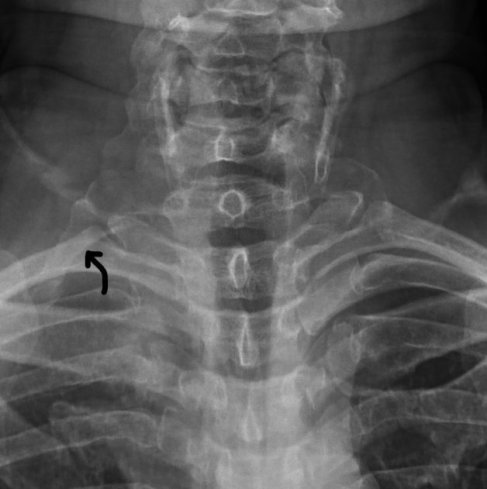

-Direk boyun grafisi: doğuştan fazlada kemik varlığı araştırılır

Resim. Çıkış bölgesini sıkıştıran boyun omurundan gelen kemik yapı